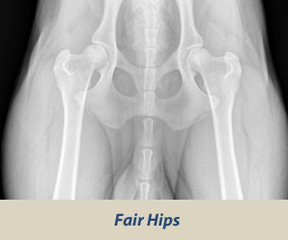

Výsledok (nález) sa označuje číslami 0-4 a písmenami A-E a je zaznamenaný pre každú končatinu zvlášť.

hips excellent hips good hips fair

A – negatívny stupeň

-anatomická pravidelnosť, žiadne príznaky dysplázie

B – prechodný stupeň

-mierna anatomická nepravideľnosť